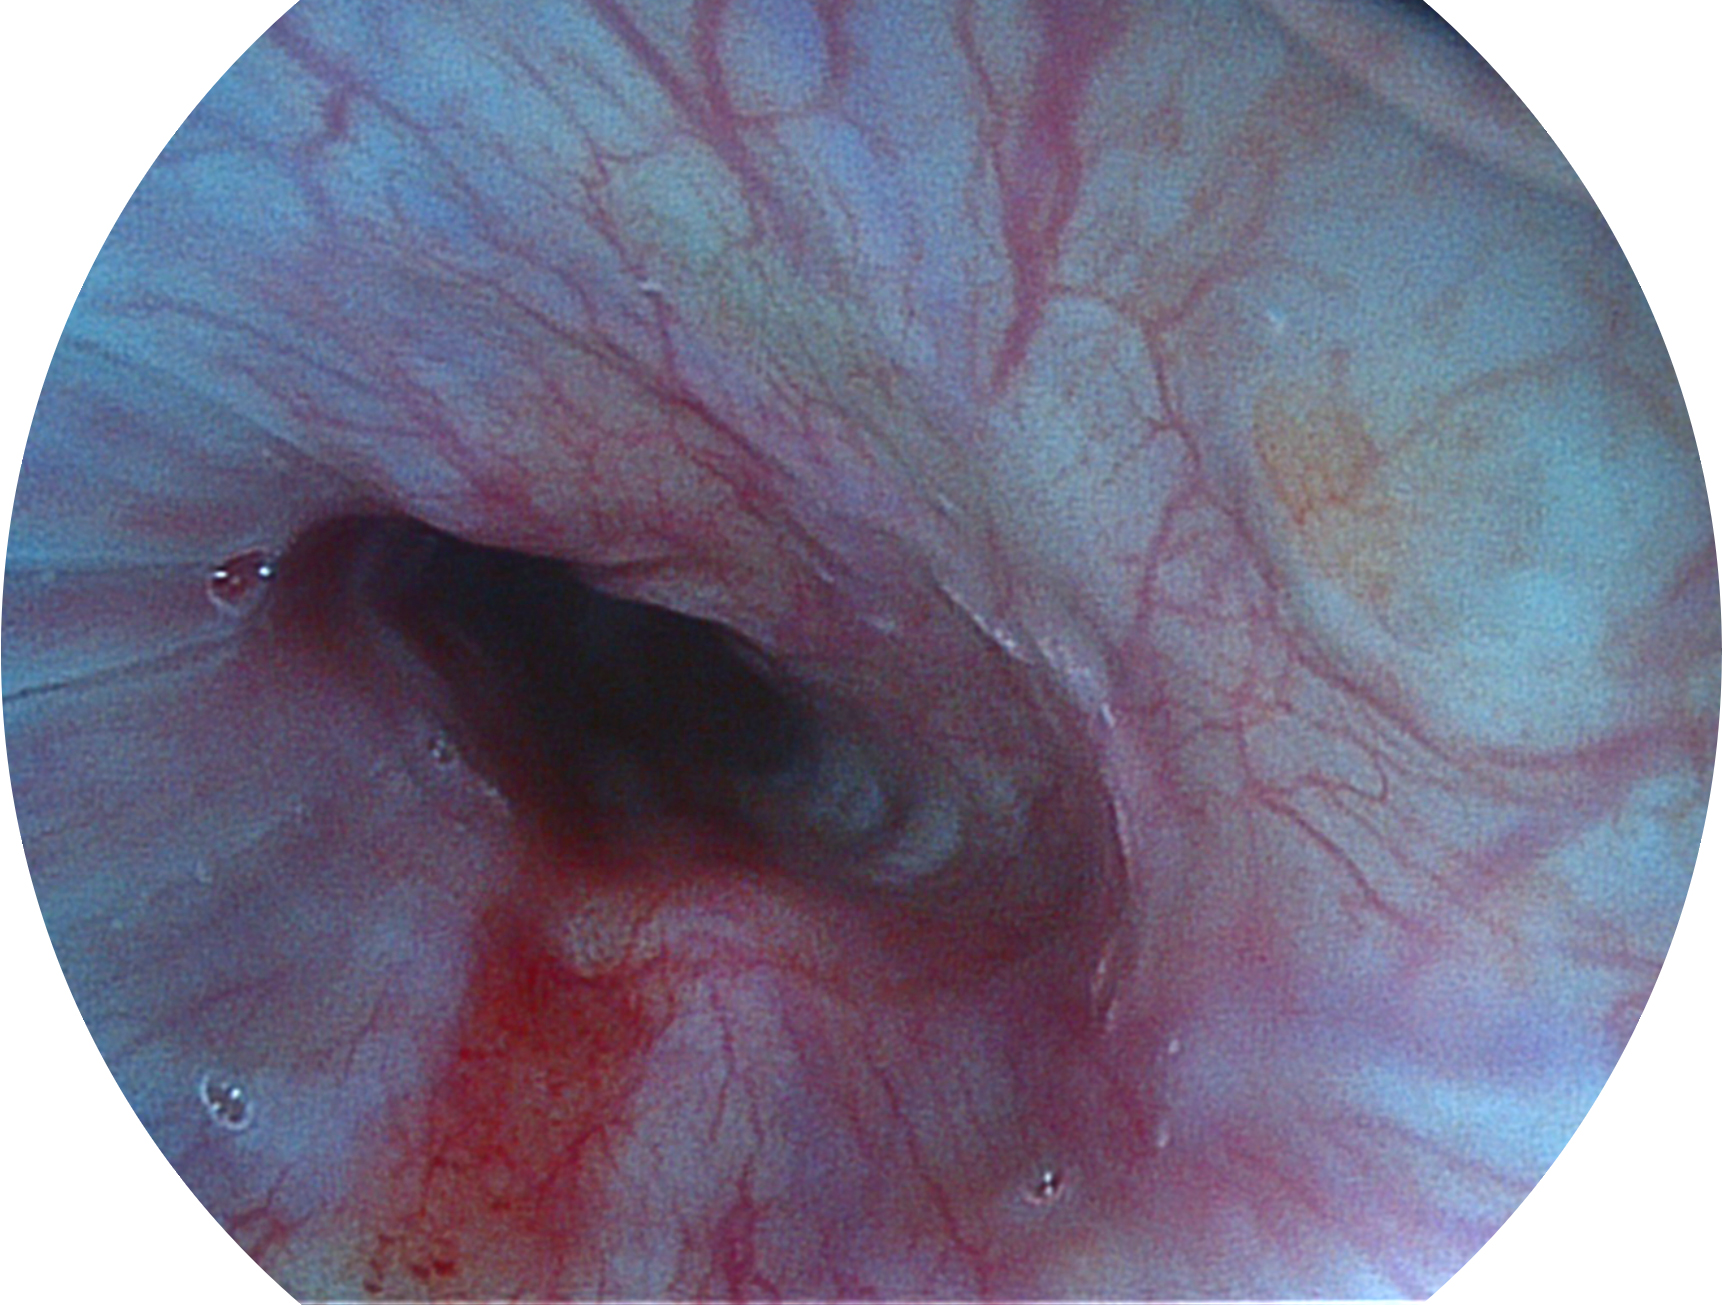

開立新開發(fā)的內(nèi)鏡染色技術(shù),主要是基于多波長LED 光源的開發(fā),VLS-55Q 四波長LED 光源是由四個不同顏色的LED光按照相應(yīng)照明模式所規(guī)定的特定發(fā)光比例進(jìn)行合束后形成,合束后形成的照明光的光譜由紅光、綠光、藍(lán)光及藍(lán)紫光這四個不同的波段范圍構(gòu)成。具有更高光譜自由度,通過光譜比例的控制,實現(xiàn)了聚譜成像技術(shù),英文全稱為“Spectral Focused Imaging, SFI”,縮寫為“SFI”和光電復(fù)合染色成像技術(shù),英文全稱為“Versatile Intelligent Staining Technology, VIST”,縮寫為“VIST”。